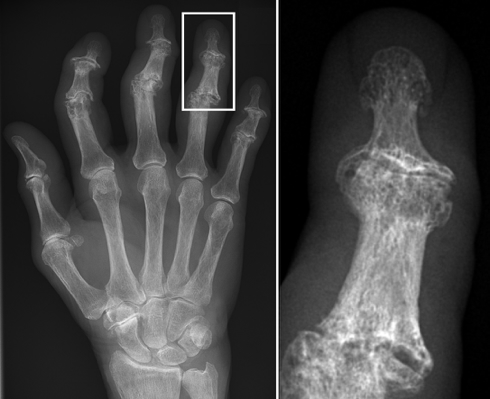

- Large, weight-bearing joints: knees, hips, spine

- Small joints: DIP (Heberden nodes), PIP (Bouchard’s nodes), 1st MTP (bunions)

- Eburnation of bone – shiny, thickened subchondral bone

- Cartilage degeneration – roughened, thinned articular surface

- Osteophyte formation – “joint lipping” seen around joint edges